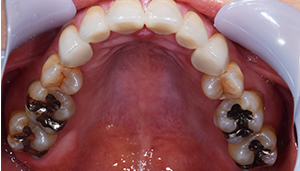

治療前

治療前 パノラマレントゲン写真

担当医師所見:

銀歯の詰め物の下で虫歯があり、神経を取り除く必要が高いことがわかります。

銀歯が多々奥歯につめられており、噛み合わせもきちんと見ていく必要があります。

奥歯の詰め物の治療終了後

奥歯の治療が終わったところです。前歯の治療に行く前に、噛み合わせをしっかり確認します。